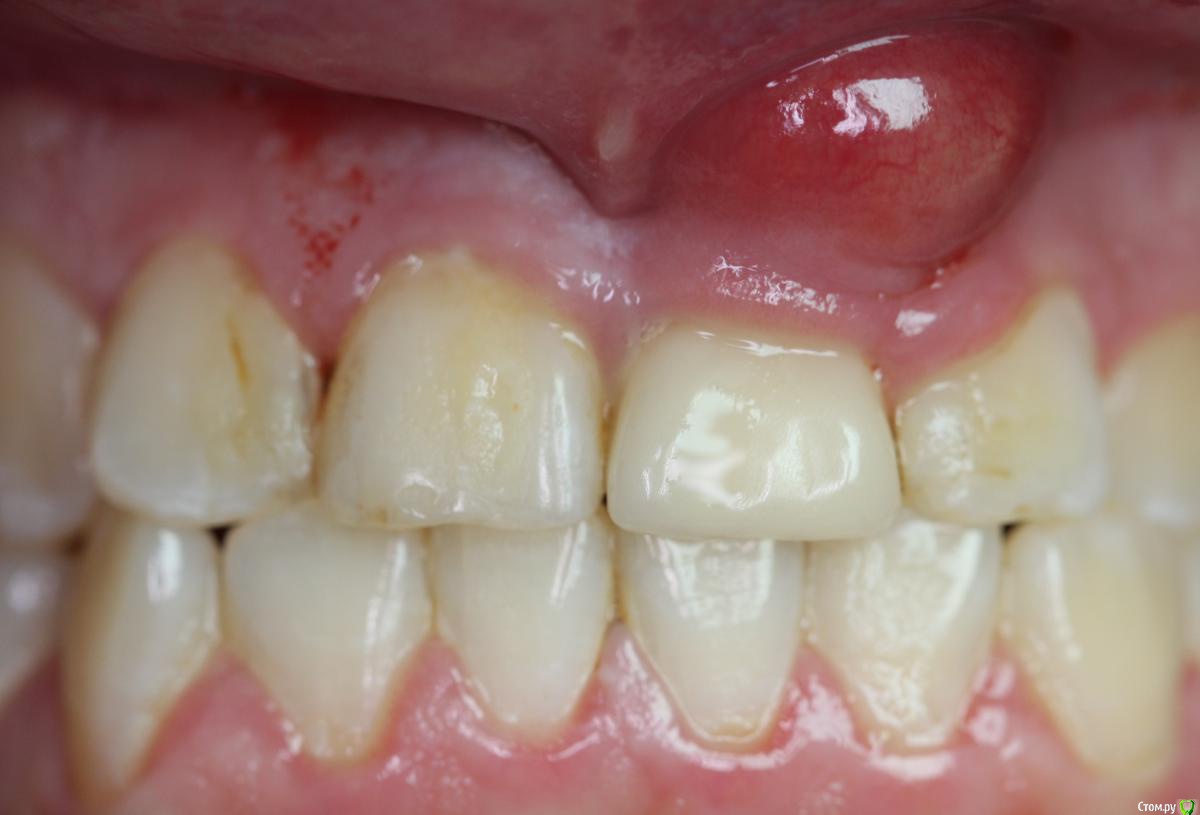

Zorrro Опубликовано 29 февраля, 2016 Автор Поделиться Опубликовано 29 февраля, 2016 (изменено) Через два дня пациент меня неприятно удивил.И ,безусловно,правильно было бы отменить операцию и ограничиться удалением,но… Вот такой был сюрприз под носом с нечищенными зубами.Обговорив риски,перекрестившись начали.Во время операции фото не делал.Слизистая в проекции 21 была сильно истончена острым гнойным процессом,буквально светилась.в итоге после эвакуации гноя промыл фурацилином,установил анкилос А11,подсыпал остеопласт вестибулярно и укрыл это всё сст из бугра в качестве мембраны.ещё один сст пошёл навременный абатмент в виде "шашлыка".Через 10 дней Через 4 месяцас рекомендацией замены пломбы на 12 у своего доктора мы ипопрощались.пациентка осталась глубоко удовлетворённой,а это главное. Изменено 29 февраля, 2016 пользователем Zorrro 4 Ссылка на комментарий